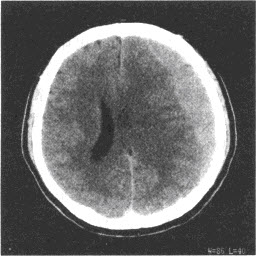

- 单项选择题患者,男,24岁,头部被球击中,1周后出现持续性头痛、头晕,结合CT图像,最可能的诊断是()

D、亚急性硬膜下血肿

- D